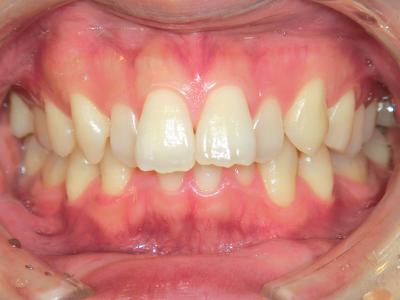

ないき歯科クリニックでは、これからあごが成長していくお子様や、歯並びが気になる成人の方など、さまざまな年代の方に対して矯正治療を行っています。

歯並びやかみ合わせを正しく整えると、笑顔や発音の自信につながり、むし歯・歯周病・口臭の予防にも役立ちます。

【4】矯正治療

矯正装置を装着し、調整しながら少しずつ歯を移動させ、歯並びを整えていきます。